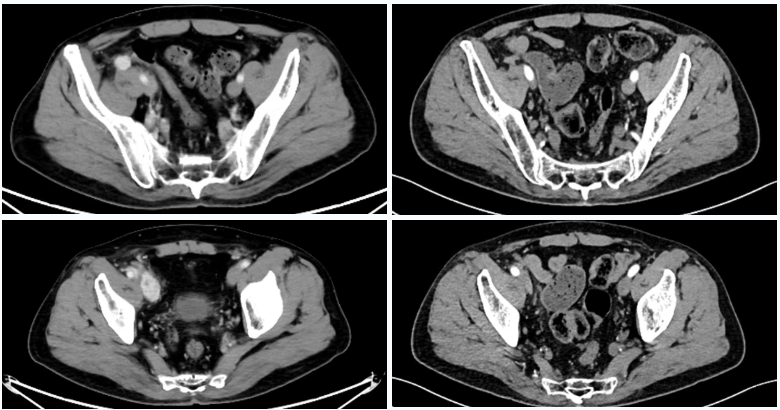

△2025年8月疗效评估时患者CT检查(右)较基线(左)对比

△2025年8月疗效评估时患者CT检查(上)及SPECT骨扫描(下)提示新发胸椎转移